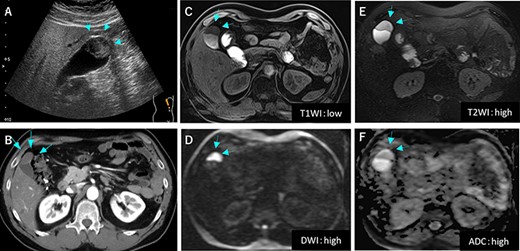

Preoperative image findings; (A) Gallbladder tumor was at gallbladder body by abdominal ultrasonography; (B) CT scan revealed slightly enhanced tumor located at gallbladder fundus; (C–F) On MRI, the tumor had high signal in both of T2 and diffusion weighed image and low signal in both of T1 and apparent diffusion coefficient.

A 53-year-old man with history of liposarcoma had gallbladder tumor detected during routine ultrasonography (Fig. 1A) and was referred to us. He was first diagnosed as leg liposarcoma 5 years before and underwent complete resection. Despite of history of liposarcoma in his leg, he never developed any abdominal symptoms. Laboratory tests were unremarkable including carcinoembryonic antigen and carbohydrate antigen 19-9 (CA19-9) within their normal limits. Computed tomography (CT) scan demonstrated slightly enhanced 4-cm tumor located at gallbladder fundus (Fig. 1B). On magnetic resonance imaging (MRI), the tumor had high signal in both of T2 and diffusion weighed image and low signal in both of T1 and apparent diffusion coefficient (Fig. 1C–F). Based on these findings in imaging studies, our working differential diagnosis included liposarcoma and hemangioma rather than adenocarcinoma, and we recommended laparoscopic cholecystectomy. In the exploration, the tumor in the fundus appeared without serosal invasion (Fig. 2). Intraoperative ultrasonography revealed the tumor was contained in the gallbladder without infiltration into the liver, and in fact there was a distance between the liver bed and the tumor. Sonazoid enhanced ultrasonography ruled out liver metastasis and thus, we proceeded to laparoscopic cholecystectomy as planned. When the gallbladder was opened, yellowish white tumor was confirmed in the submucosal layer with the overlying mucosa intact (Fig. 3A). Histopathological examination revealed, this tumor as myxoid liposarcoma consisting of lipoblasts and round cells. There was no necrosis and proliferations of spindle and round cell component were identified in the background of myxoid stroma (Fig. 3B). These histological features were similar to the ones for the sarcoma in his leg that was resected before. The patient’s postoperative course was uncomplicated and was discharged home on Day 3. The adjuvant therapy was elected not to be given and he was placed on imaging surveillance with CT scan in every 3–6 months. In 16 months after this operation, he developed disease recurrence in the left popliteal fossa. There was no recurrence to date in the abdominal cavity at 28 months after the operation, he was alive with disease.